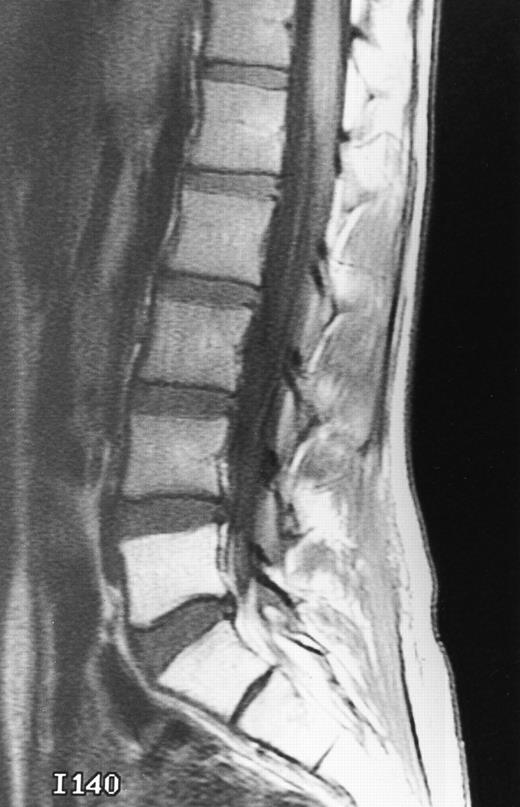

T1-weighted (500/11, TR/TE) sagittal MR images of the lumbosacral spine in a 45-year-old woman before (A) and 40 days after (B) bone marrow transplantation for multiple myeloma. There is a diffuse MR pattern of marrow involvement in (A) (bone marrow plasma cells, 50%; monoclonal protein, 6.0 g/dL). On the posttreatment image, there is definite reinstitution of fatty marrow in the spine and, in particular, around the basivertebral veins, in keeping with partial response to treatment (bone marrow plasma cells, 0.5%; monoclonal protein, 1.6 g/dL).